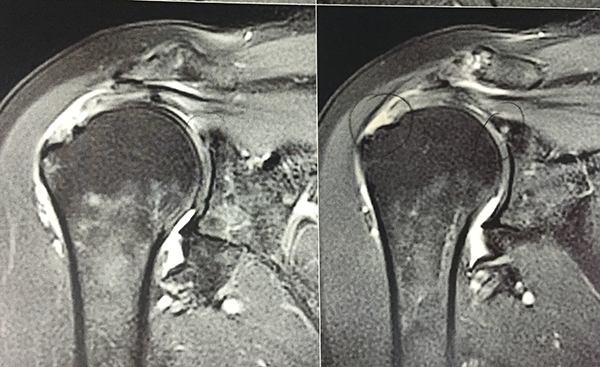

Tear size was defined via preoperative magnetic resonance imaging (MRI) and/or during surgery with a measuring probe; when both were available, surgical measurements took precedence over MRI data (figs. 1, 2, and 3). Tears were classified according to Cofield et al. as small (<1 cm), medium (1–3 cm), large (3–5 cm), or massive (>5 cm).1, 9

Figure 2: Magnetic resonance image (coronal view) showing a tear in the supraspinatus tendon.